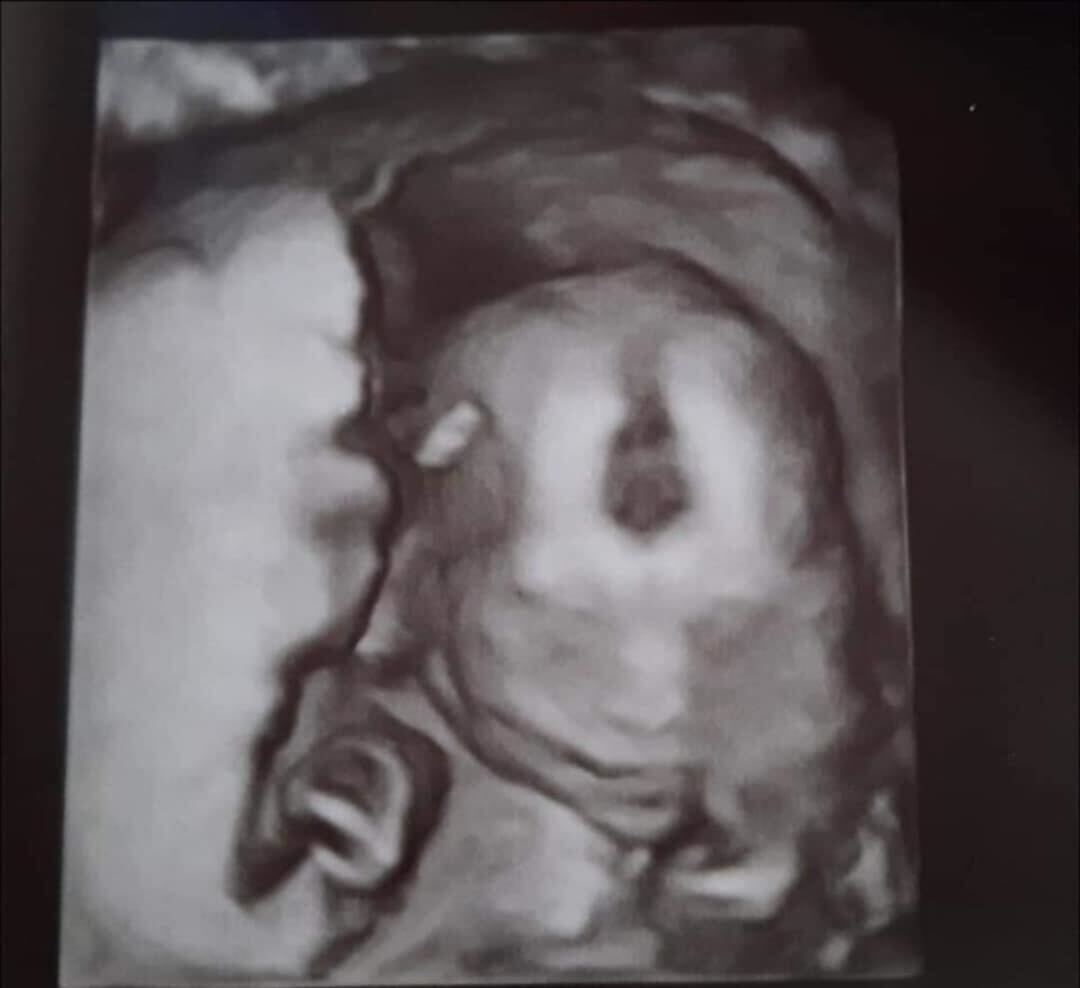

Oliver’s ultrasound uncovered paralysis, a hole in his heart, and a missing kidney, among other things. Photo courtesy Heather Martell

That gut feeling was right. The 19-week ultrasound revealed crushing news: there were abnormalities in the fetus, with the head, spine, and heart. Another scan at 20 weeks confirmed everything. The baby was likely paralyzed from the chest down, did not have a right kidney, and his left kidney was severely deformed. Heather was told Oliver wouldn’t survive long after birth—and would suffer in the process.